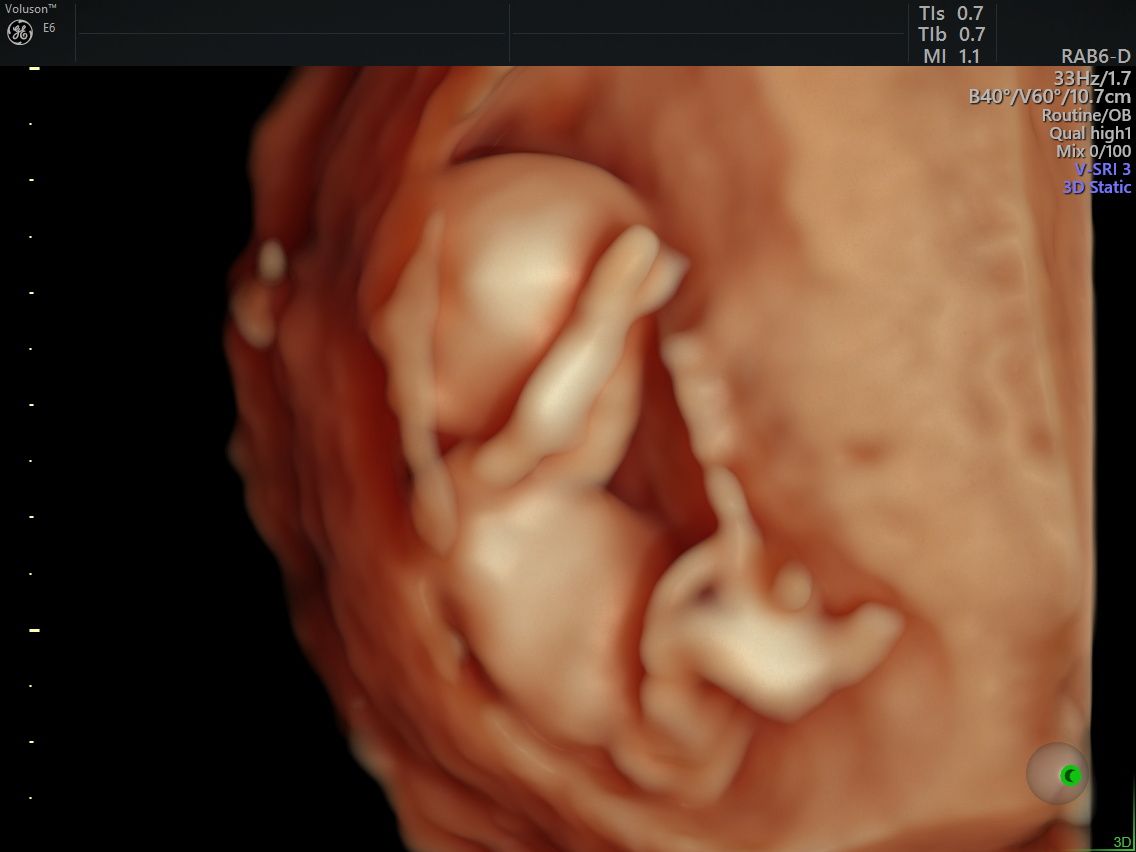

Realizo estudios con tecnología avanzada para detectar posibles complicaciones durante el embarazo. Entre ellos se incluyen ultrasonidos de tamizaje en el primer trimestre, ultrasonidos estructurales, seguimiento de embarazos gemelares y pruebas genéticas como ADN fetal, biopsia de vellosidades coriales y amniocentesis, que ayudan a evaluar la salud del bebé y del embarazo.

Fotos y videos